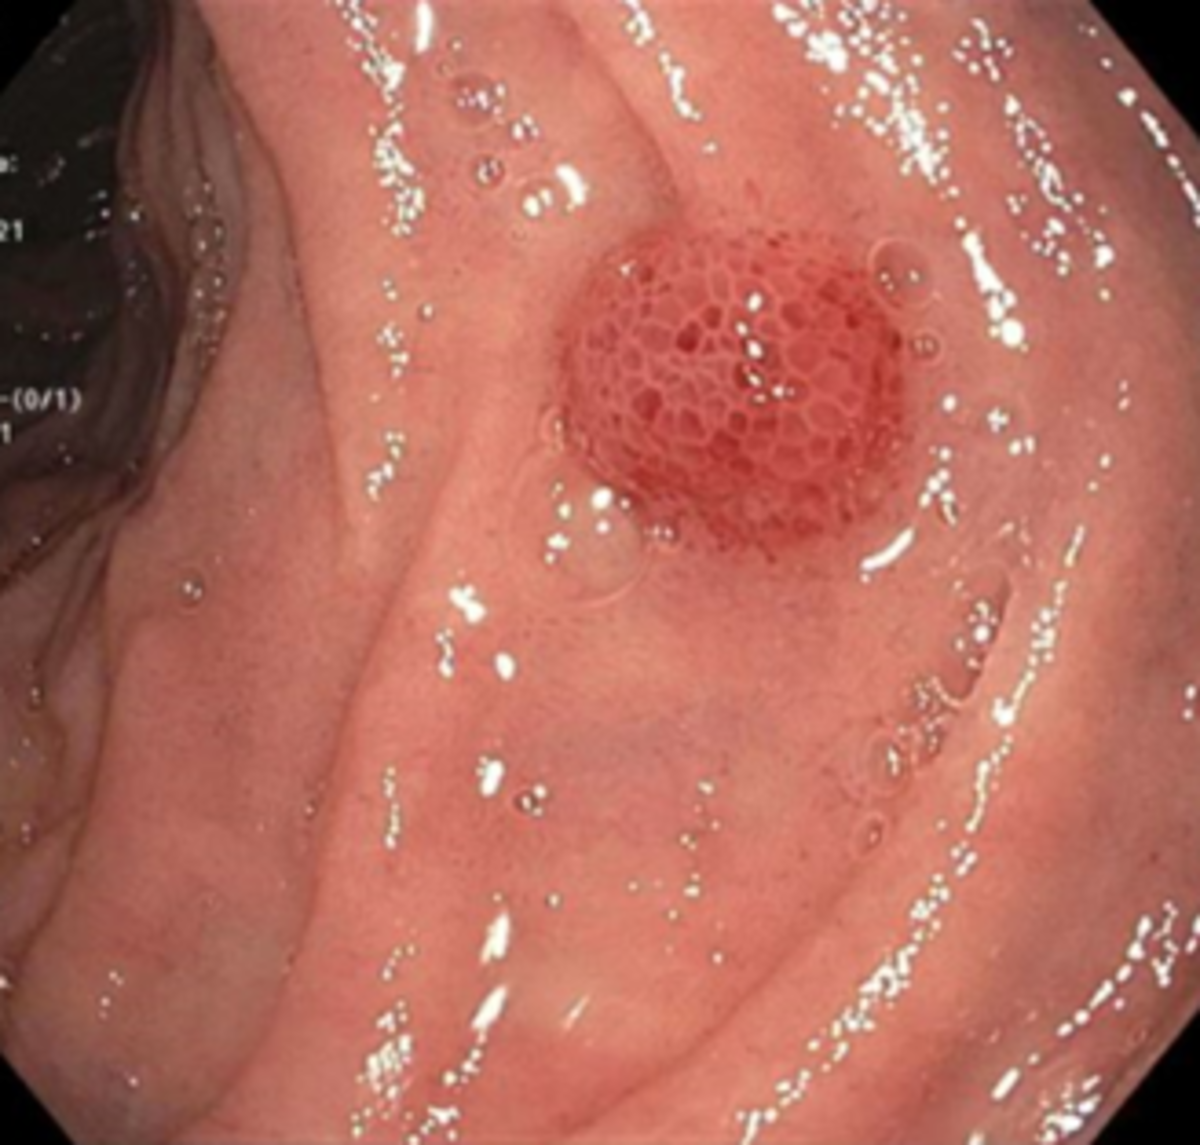

A 58-year-old man is found to have anemia. He has a history of HIV and HCV. He reports shortness of breath on exertion and constipation. He has not noticed any rectal bleeding. He has not had endoscopic workup for anemia. On physical exam, there is diffuse violaceous coin-shaped papulosquamous rash on trunk and extremities [figure A]. Laboratory testing reveals hemoglobin 8.8 g/dL (normal: 14-17 g/dL), MCV 82 fL (normal: 80-96 fL), CD4 count 16 cells/µL (normal: 677-1401 cells/µL). His liver chemistry was normal except low albumin levels of 2.1 g/dL (normal: 3.5-5.0 g/dL). EGD- reddish, nodular lesion in second part of duodenum [figure B]. IHC- human herpesvirus 8 on biopsy specimen. What is the most appropriate next step in the management of this patient?

• Kaposi Sarcoma (KS) with cutaneous and gastrointestinal manifestations - can have GI w/o skin

• Gastrointestinal lesions can be asymptomatic or can present with weight loss, abdominal pain, nausea and vomiting, upper or lower gastrointestinal bleeding, malabsorption, intestinal obstruction, and/or diarrhea.

• Gastrointestinal KS lesions are typically hemorrhagic nodules that can be either isolated or confluent and may occur in any portion of the gastrointestinal tract.

• Dx: histopathology with biopsies positive for human herpesvirus 8

• Tx: start antiretroviral therapy (ART). Some patients will also require chemotherapy